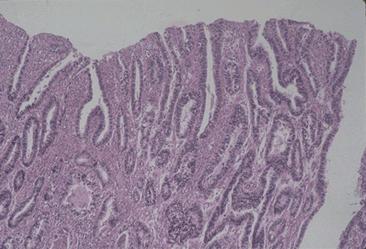

Criteria of Hist.ClassificationMalignant epithelial tumor/Adenocarcinoma

LocationStomach/Antrum

Technique, MethodHistology

Macroscopic TypesType 1 Protuberant (polypoed) type/

Size40 -

Depth of Tumor Invasionmuscularis propria